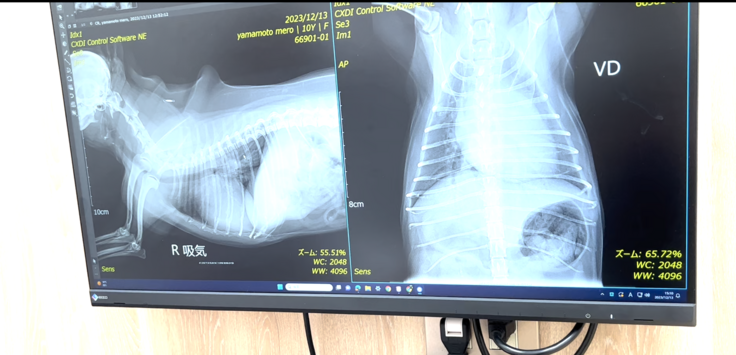

手術に向けて検査(12月13日)

大きな総合病院へ行き、メロが外科手術に適合するのか検査を行ってきました。

↑レントゲン写真、心臓が正常の子に比べて拡大し、肺と気道を圧迫してしまっている状態。